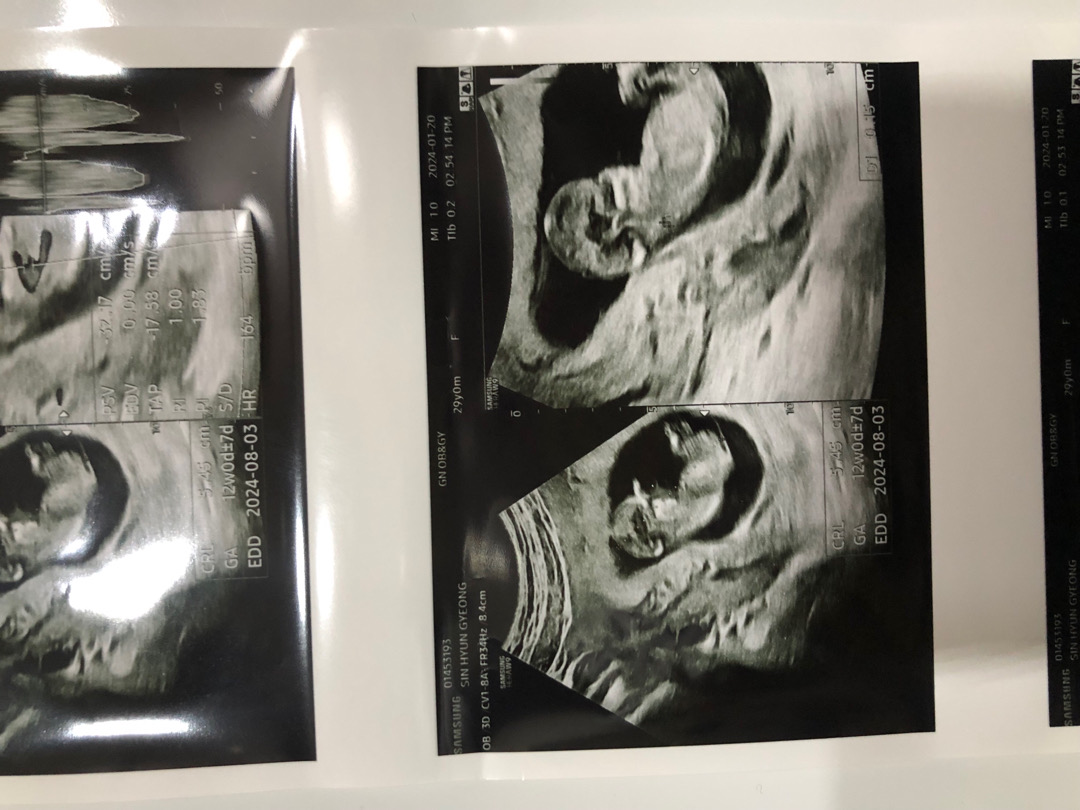

다리에 가려져 잘 안 보이네요~!

각도법 볼줄을 잘 모르는데여...ㅎㅎ

혹시 볼줄 아시는분 있으면 함 봐주세용~~~!~!~!~!~

최근 유트루님 브이로그에서 봤는데 척추랑 꼬리가 평행이면 딸이고 각도가 벌어지면 아들이래요!